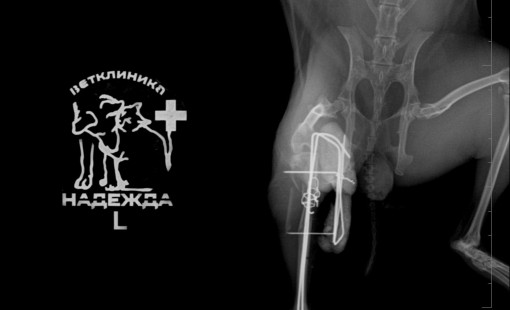

Случаи из практики

Ветеринарная клиника Надежда

За более чем 30-ти летнюю практику наши ветеринары сталкивались в различными случаями болезней и травм животных. Это дало нам огромный опыт в лечении и реабилитации. Мы беремся даже за самые сложные случаи! С любовью и заботой относимся к животным, стараемся сделать так, чтобы они испытывали минимум дискомфорта во время лечения и реабилитации.